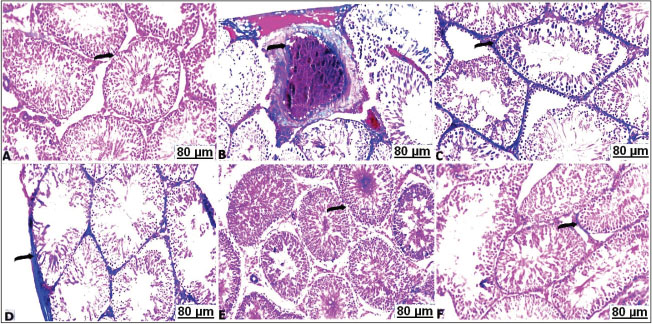

BPB stain results

A positive BPB reactivity was noticed with a dark bluish discoloration in the control testes, accordingly all the seminiferous tubules were characterized by a sharp content of total protein (Fig. 6A). CCl4 treated rats; most of the seminiferous tubules showed a marked depletion with a lower content of total protein (Fig. 6B). In the CCl4 treated rats with soybean, moderate to marked reaction was observed in the seminiferous tubules in a dose-dependent protective impact, the activity of the testicle cells showed a moderate improvement with amount of total protein (Fig. 6C and D).

Fig. 6. Transverse sections of testes with BPB of the control and treated groups: (A) control testes showing strongly reacted protein contents (arrow). (B) CCl4-exposed testes showing pale protein staining (arrow). (C) CCl4-exposed testes+10% soybean showing well-organized protein contents (arrow). (D) CCl4-exposed testes+30% soybean showing detectable stained protein elements (arrow).